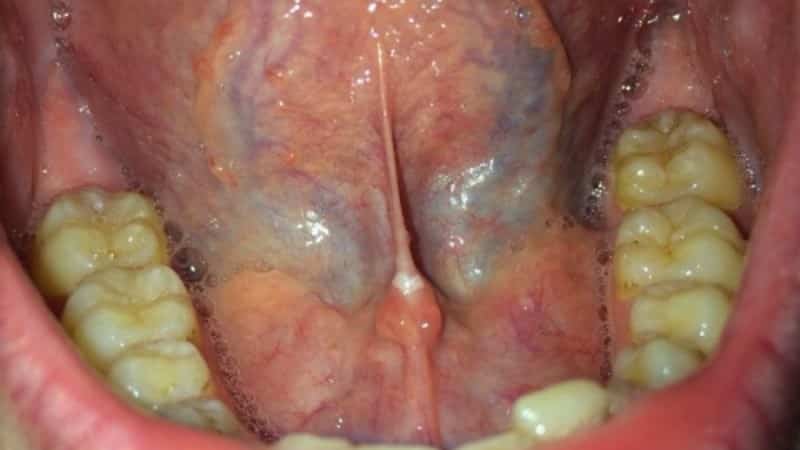

Воспаление уздечки под языком, или френит, может проявляться различными симптомами, которые могут варьироваться по степени выраженности. Основные признаки воспалительного процесса включают:

- Отек: Воспаление может приводить к отеку уздечки, что делает ее более заметной и может затруднять речь и глотание.

- Покраснение: Участок вокруг уздечки может быть покрасненным, что свидетельствует о воспалительном процессе.

- Кровоточивость: В некоторых случаях возможно появление небольших кровотечений, особенно если уздечка повреждена или травмирована.

- Визуальный осмотр: Специалист осматривает уздечку и окружающие ткани на наличие покраснения, отека, язв или других изменений.

- Пальпация: При необходимости врач может провести пальпацию для определения болезненности и степени отека.